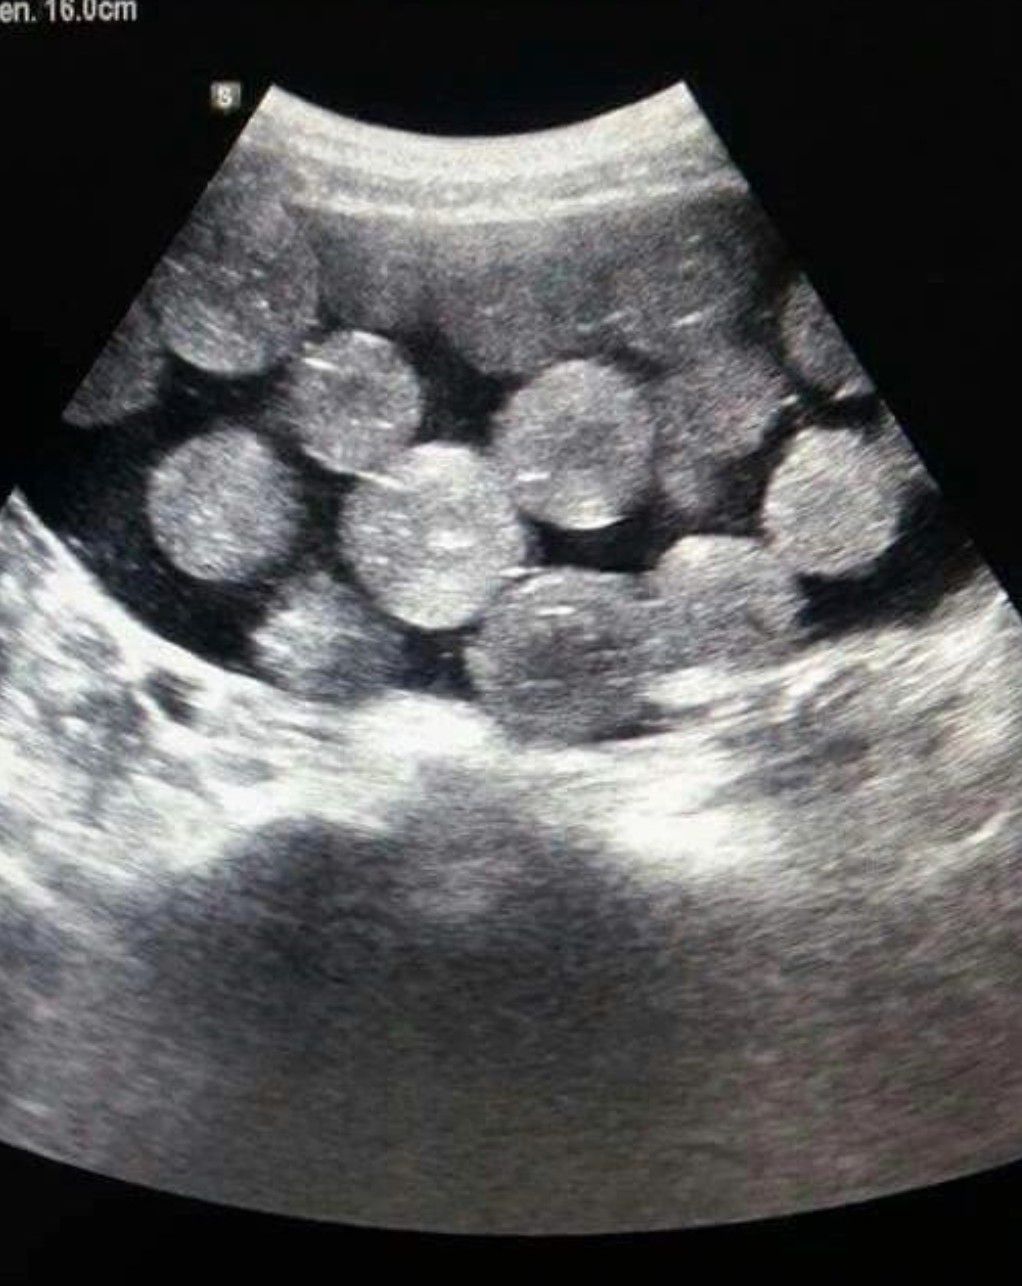

Identify the Pathology

Identify the pathology in the given radiograph.